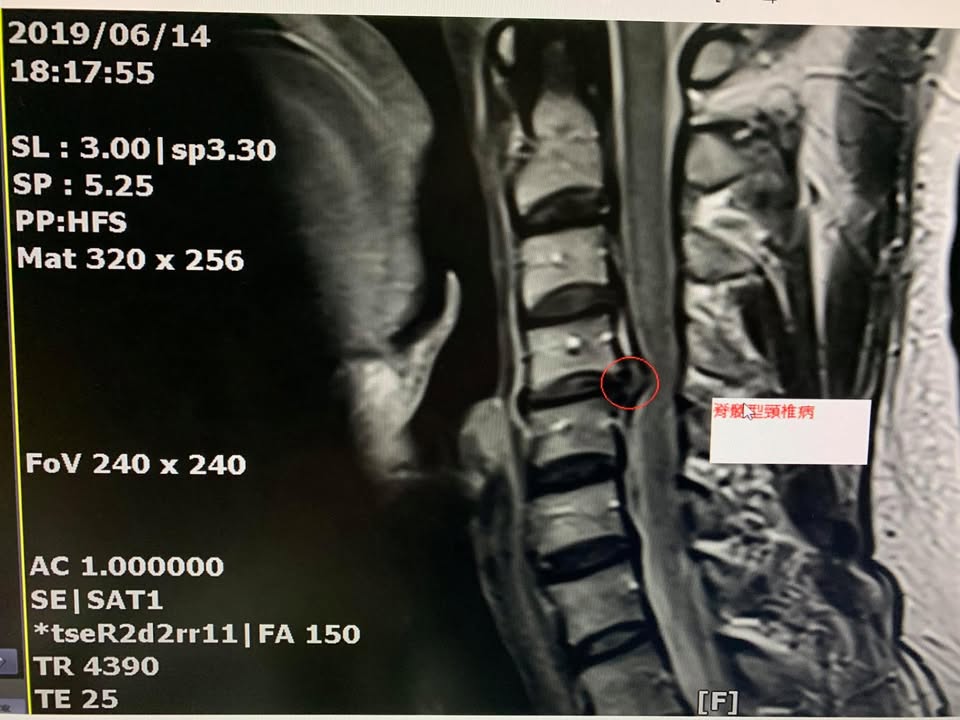

住在宜蘭的黃先生抱怨左邊頸椎痛連上臂,這兩個月嚴重惡化,今年六月十四號去陽明大學附設分院拍攝核磁共振,mri證實c4c5椎間盤突出壓迫脊髓,骨科醫師強烈建議開刀處理,門診檢查發現頸椎稍微往後仰立刻誘發麻痛,仔細詢問肩頸已經痛很長一段時間了,一直到今年才受不了,工作的時候很明顯感覺肩膀痛到手臂來,之前接受骨科小診所復健拉脖子拉了一年以上,效果還是不如預期,這次原本安排七月四號要開刀,在七月二號來到診所接受脊椎整合中醫微創療法,徐醫師告訴他如果前面兩三次治療有改善,前面兩三次就有改善可以跟醫院再延緩一段時間再開,非常幸運跟順利,到了第五次治療後有明顯突破,肩頸疼痛大幅度下降,黃先生直接將手術大刀取消掉,徐醫師囑咐他這次好了不代表以後永遠會好,重點是姿勢跟工作時間,更要好好訓練頸椎的力量!這樣才能永保安康

診斷:頸椎第四第五椎間盤壓迫硬膜囊

跟神經根